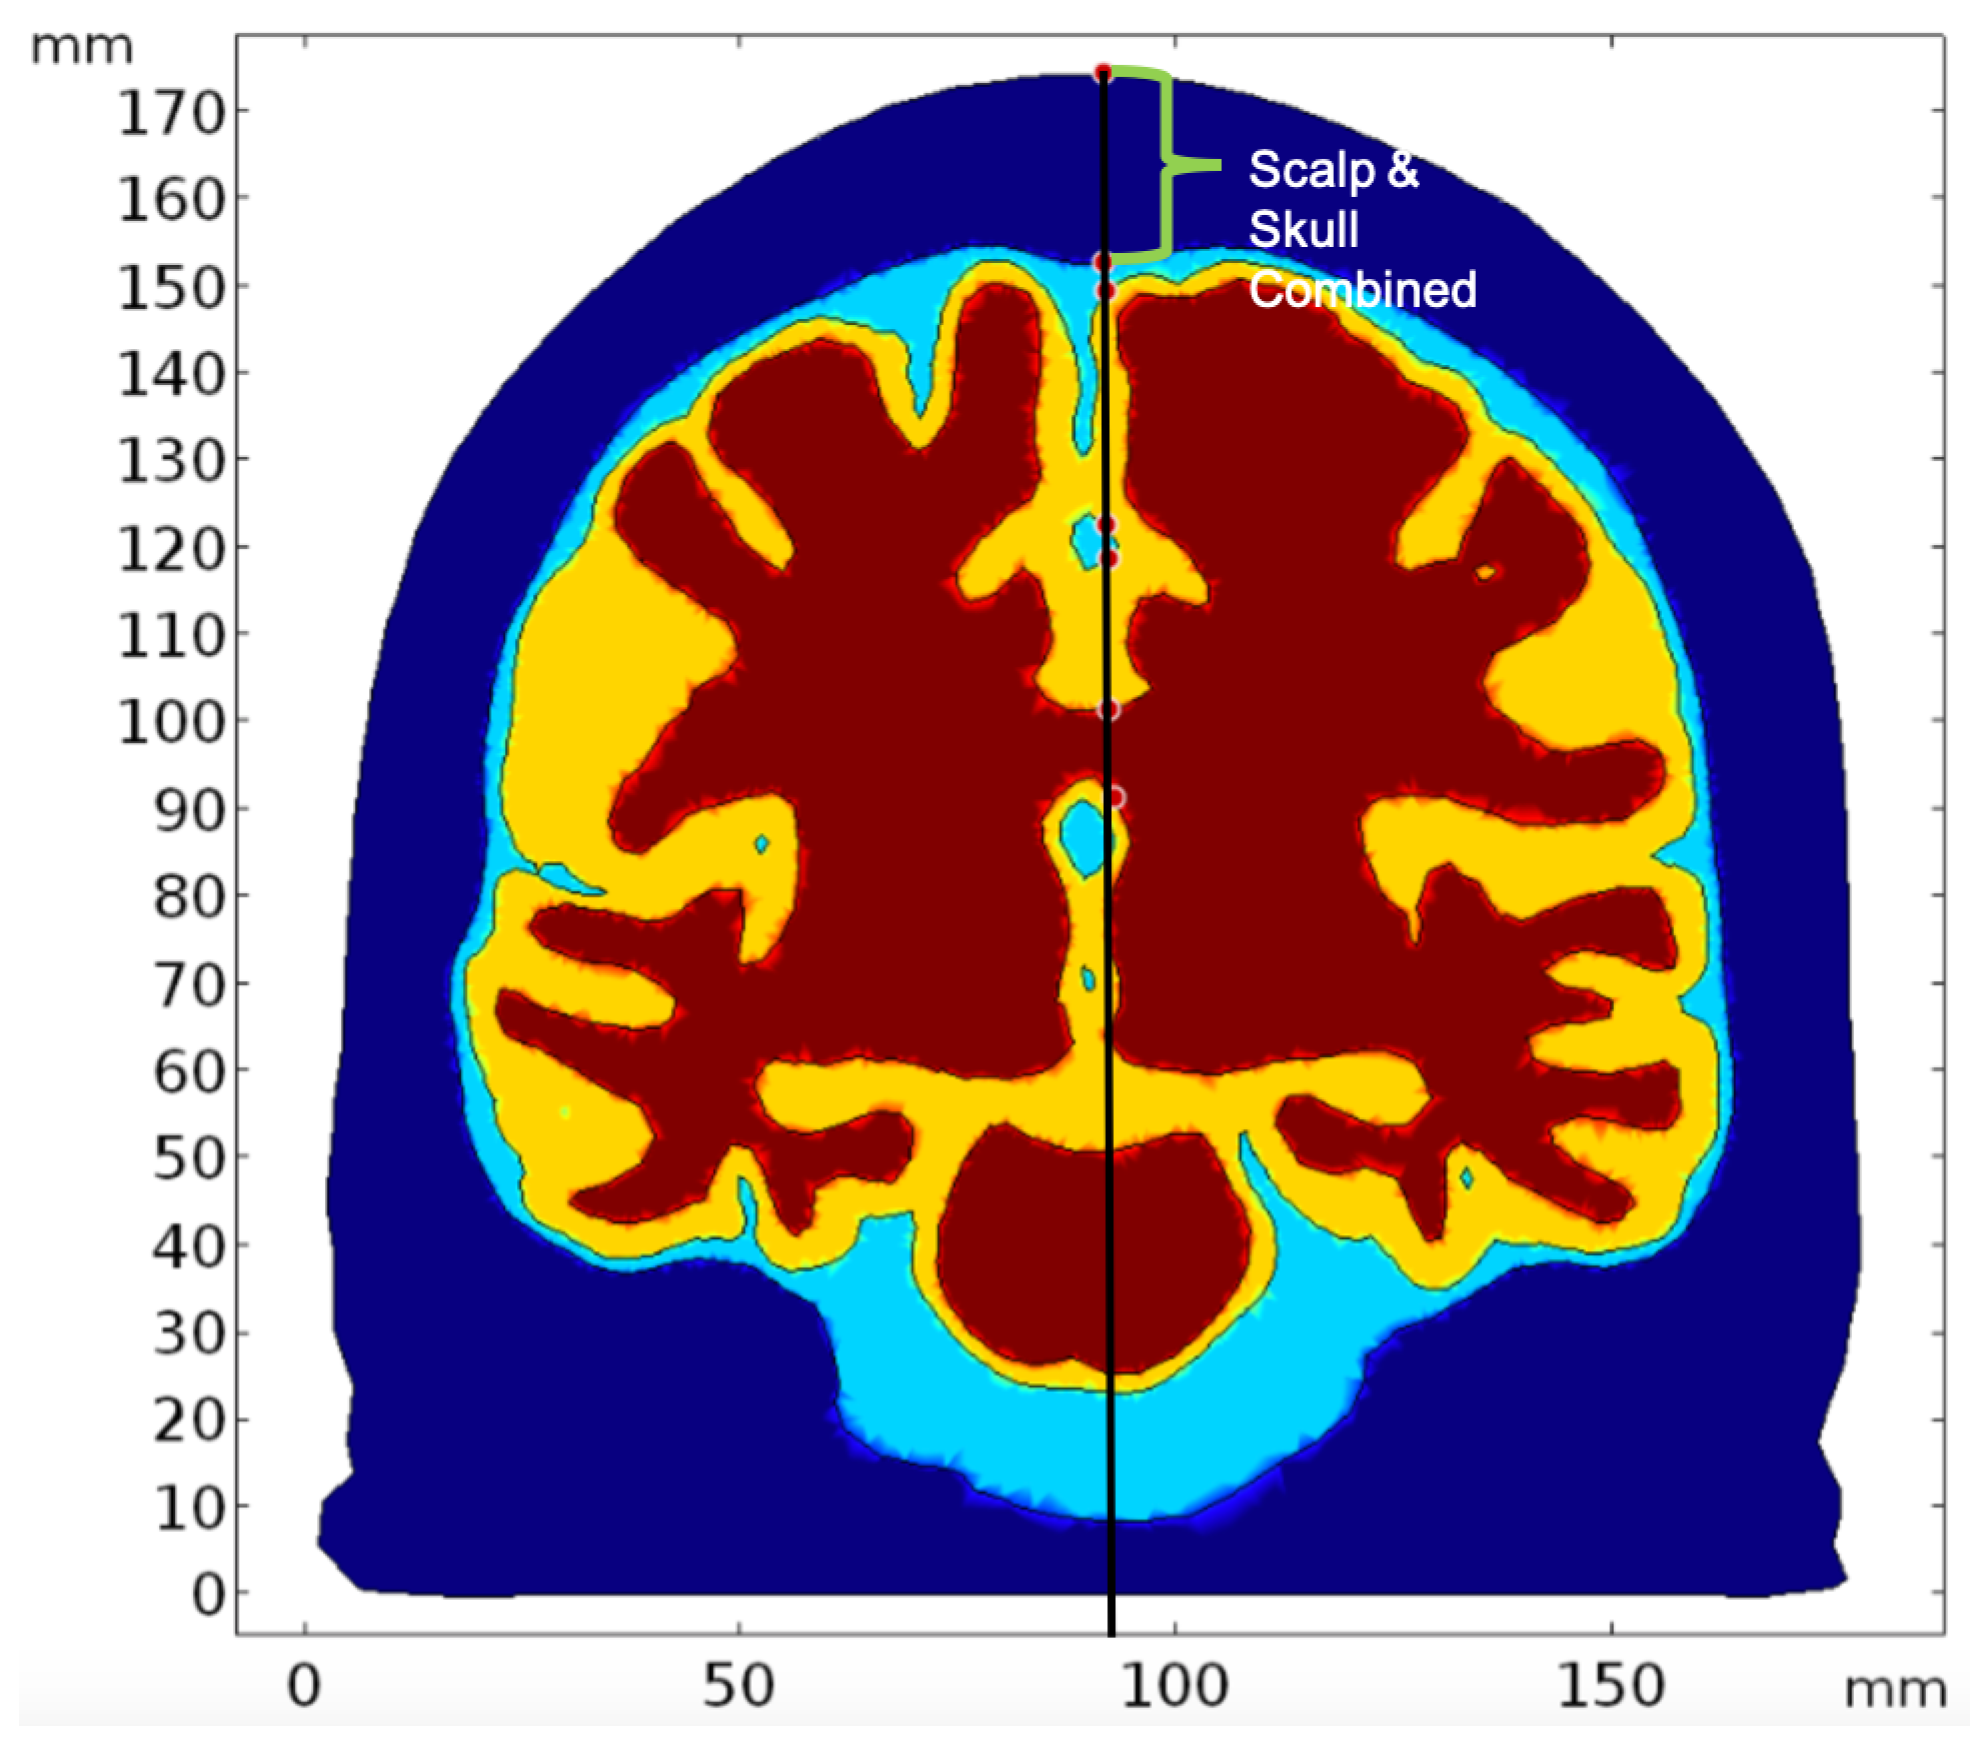

2.2. Geometry and Domain Assignment

- Domain 1: Combined scalp and skull

- Domain 2: Cerebrospinal Fluid

- Domain 3: Gray Matter

- Domain 4: White Matter